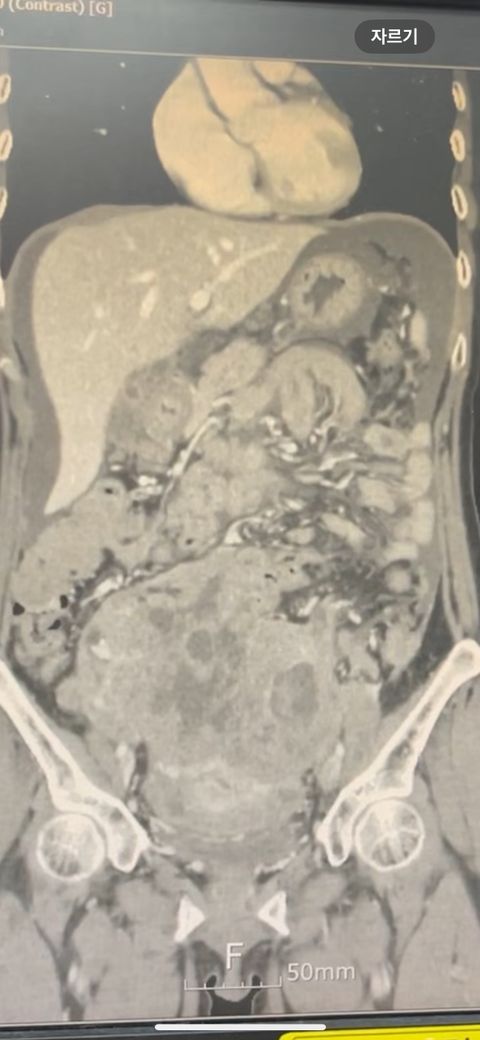

복부 ct (contrast) 영상 판독해주세요!!

어제 복부 ct 촬영하였는데 판독 하려면 시간이 걸려서 미리 알 수 있을까요? 지금 증상은 윗배가 많이 나왔고 허리 아프고 조금만 밥 먹어도 배부른 상태입니다..

어제 말씀드린대로 자궁 쪽에 불규칙한 음영들이 보이고 있어 물혹이 있는 것으로 의심해 볼 수 있으며, 이외에 복부에 가스가 조금 차있거나 비장이 약간 커져 있는 듯한 모습이 보이나 일부 단면만으로 유추한 것이라 판독 상 틀릴 가능성도 있겠습니다.